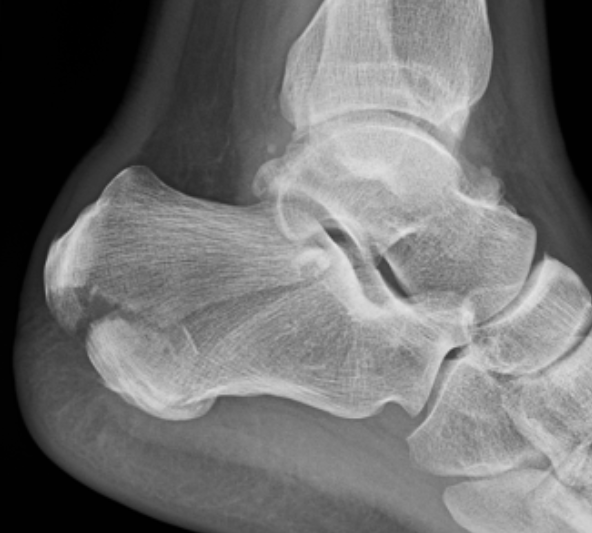

Essex-Lopresti classification intra-articular fractures

- joint depression

- tongue-type

Tongue type

- involve posterior subtalar joint

- secondary fracture line extends posteriorly into calcaneal tuberosity